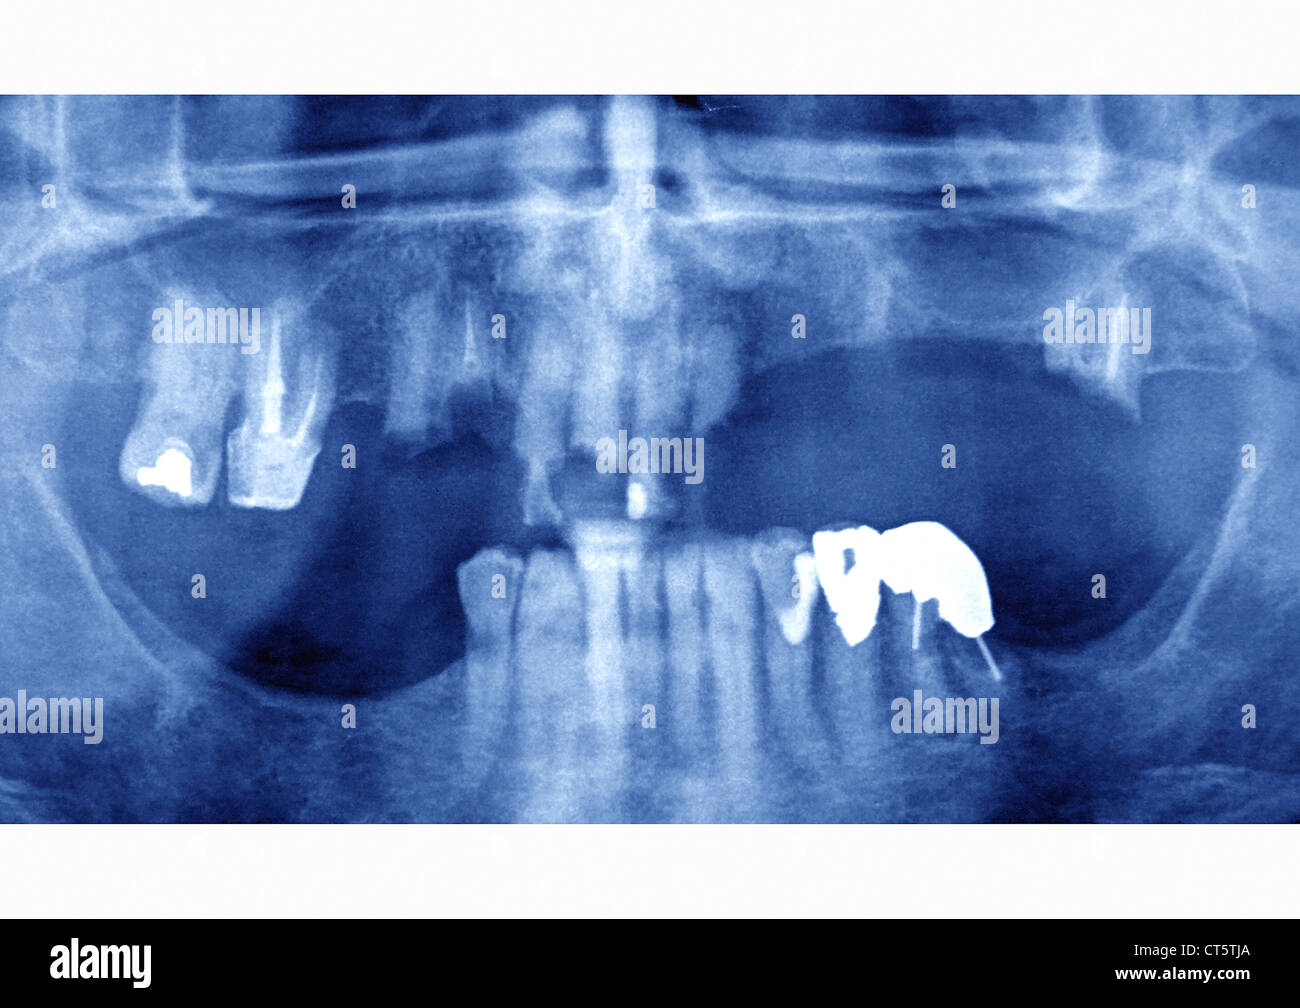

from www.bluewaterdentists.com

Imaging of the oral cavity can be limited by artefacts from dental amalgam and opposed. Restorative materials that are clearly radiopaque include amalgam, cast gold, cohesive gold, nonprecious alloys, and the. The fda is providing information on dental amalgam fillings for patients and dentist, to include information on benefits and risks of. X‐ray examination detected caries in 100% of the suspected cases for amalgam and composite fillings.

Digital Dental Xrays Blue Water Dental Langley Dentist

Digital Dental Xrays Blue Water Dental Langley Dentist Amalgam Dental Xray Restorative materials that are clearly radiopaque include amalgam, cast gold, cohesive gold, nonprecious alloys, and the. The fda is providing information on dental amalgam fillings for patients and dentist, to include information on benefits and risks of. Imaging of the oral cavity can be limited by artefacts from dental amalgam and opposed. X‐ray examination detected caries in 100% of the. Amalgam Dental Xray.